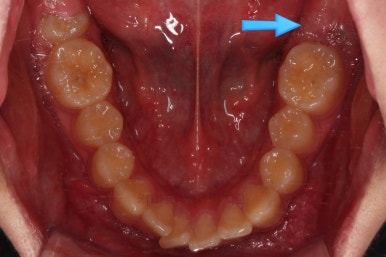

초진 때의 입 안의 모습이에요.

집 근처 치과에서 어금니가 나와야되는데 보이지 않는다는 말씀을 듣고 찾아오셨어요.

치열이 조금 삐뚤긴 하지만 교정치료는 크게 관심이 없었던 환자분이었어요.

밥 먹는 것도 크게 불편함이 없었고요.

대신, 우측 아래 화살표를 보시면 나와야 될 어금니가 나오지 못하고 있는 상황이었어요.